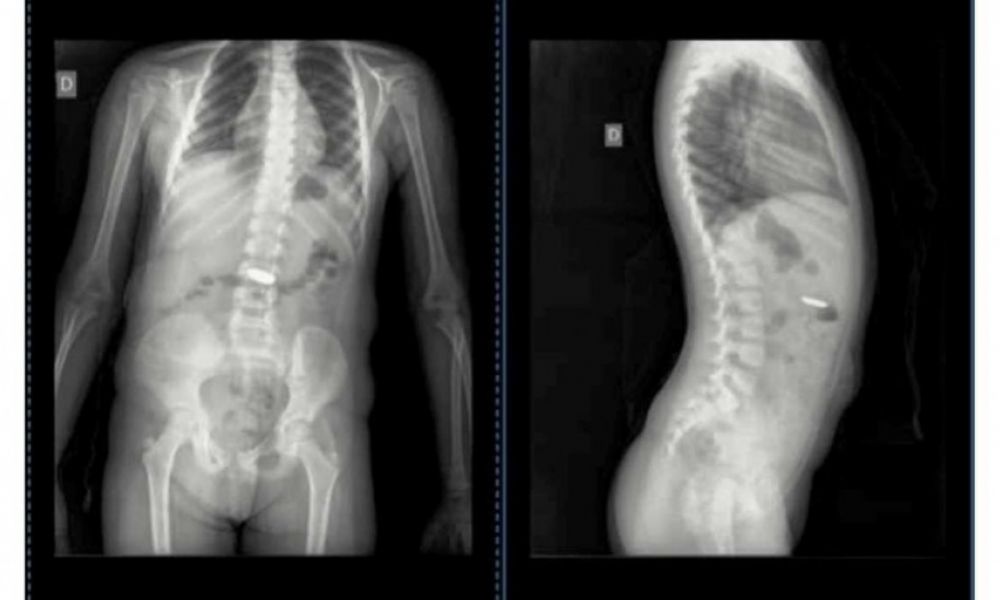

La nena tiene 4 años y tuvo la pila "botón" en su estómago durante 4 días. Sólo uno de los profesionales consultados pudo "ver lo que pasaba", contó la mujer. La nena, que se había tragado la pila "botón" el jueves pasado, fue llevada al Hospital de Niños de La Plata, donde le realizaron una endoscopia y le pudieron extraer la pila.

“Siete médicos en Chascomús vieron las imágenes de las radiografías que le hicimos a Isabella por el tema de la pila ‘botón’ que se tragó. ¡¡Sí, siete!! Cuatro en la Guardia y 3 por mensaje, solo uno, al que le pasé por mensaje ayer, supo ver lo que pasaba”, indicó la madre de Isabella en un posteo realizado en su cuenta de Facebook.

La nena, que se había tragado la pila “botón” el jueves pasado, fue llevada al Hospital de Niños de La Plata, donde le realizaron una endoscopia y le pudieron extraer la pila. La madre dijo que “por suerte decidí hacerle caso” al Dr. Jorge Ortale que detectó la presencia del elemento extraño en la radiografía de su hija.

“Pregunto ahora: ¿de siete sólo uno vio lo que pasaba? ¿Y si esa pila seguía ahí y provocaba un mal mayor a mi hija? Desde el jueves 22/6 mi hija tenía esa pila en su estómago. Gracias Doc. Jorge Ortale, usted sí supo ver lo que pasaba”, destacó la mujer.